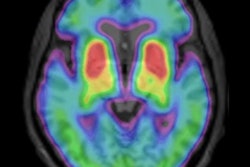

With the help of FDG-PET, researchers at the Feinstein Institute for Medical Research in Manhasset, NY, have developed an automated image-based classification procedure to differentiate patients with idiopathic Parkinson's disease from those with other brain diseases such as multiple system atrophy and progressive supranuclear palsy.

The study, published online January 11 in Lancet, concludes that the process has "high specificity in distinguishing between Parkinsonian disorders and could help in selecting treatment for early-stage patients and identifying participants for clinical trials."

Idiopathic Parkinson's disease can present with symptoms similar to multiple system atrophy or progressive supranuclear palsy, noted lead author Dr. David Eidelberg, director of the Center for Neurosciences. The researchers analyzed 167 patients between January 1998 and December 2006. The patients all had symptoms of Parkinson's disease, but their clinical diagnosis was uncertain.

For each patient, the likelihood of having each of the three diseases was calculated using multiple disease-related patterns with logistic regression and "leave-one-out" cross-validation.

After FDG-PET imaging, patients were assessed by blinded movement disorder specialists for a mean of two to six years before final clinical diagnosis. The accuracy of the initial image-based classification was then compared to the final diagnosis.

The researchers found that the image-based classification for idiopathic Parkinson's disease had sensitivity of 84%, specificity of 97%, positive predictive value of 98%, and negative predictive value of 82%.

Imaging classifications also were accurate for multiple system atrophy, with sensitivity of 85%, specificity of 96%, positive predictive value of 97%, and negative predictive value of 83%.

For progressive supranuclear palsy, the results were sensitivity of 88%, specificity of 94%, positive predictive value of 91%, and negative predictive value of 92%.